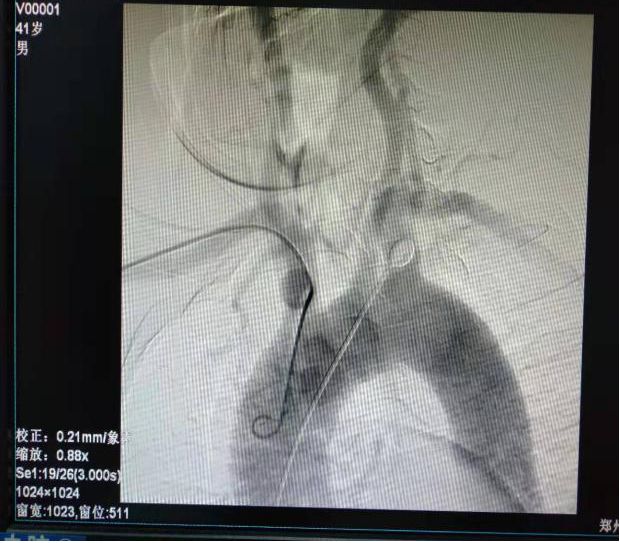

(1)2018年11月1日开展第一例主动脉弓并脑血管造影。

患者:王某 男性  41岁  城关镇